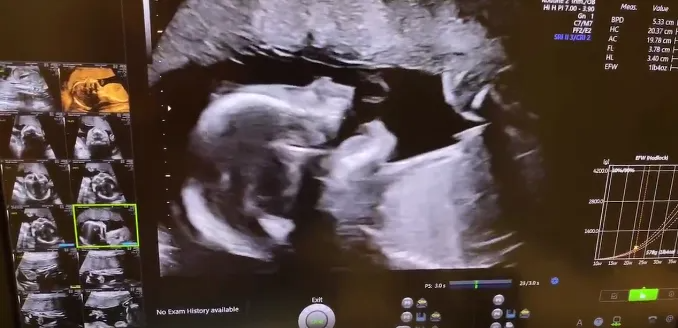

40岁的她,将生育自由掌握在自己手中!

完美的“大排畸筛查”来自广州的W女士是一位金融从业者,年轻时忙于工作一直没有时间和机会生产,等到40岁的时候突然萌生了要宝宝的想法,但备孕很久都没有成功。后来医...